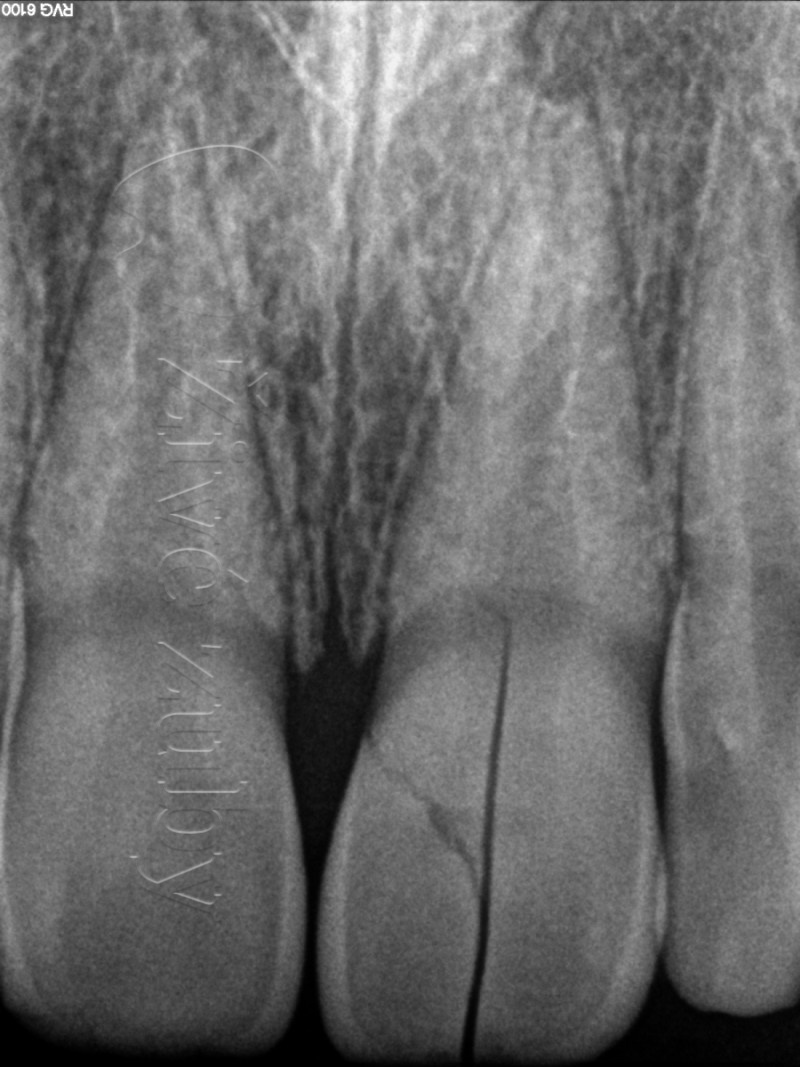

Fraktury zubů

(nekomplikované, komplikované, pulpotomie, … )

Výchozí stav  ——-  Kontrola po 2 letech